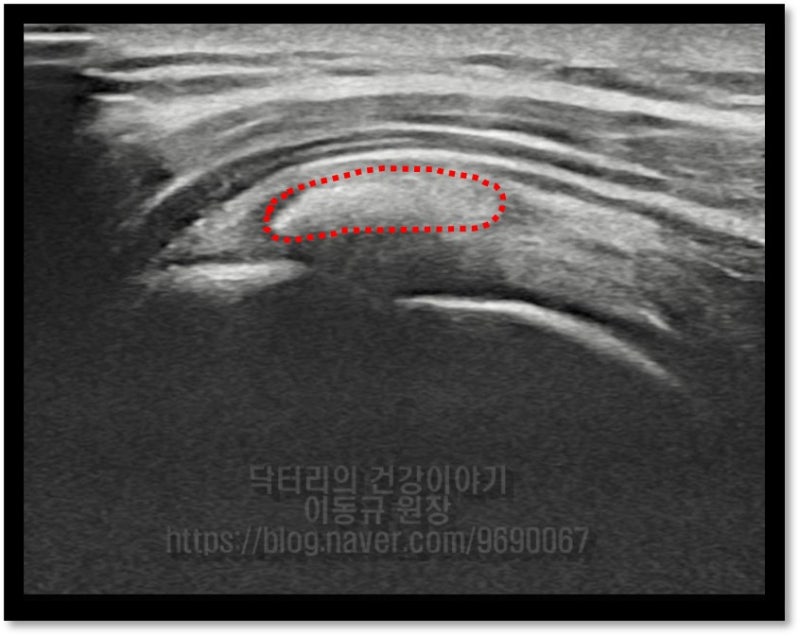

타병원에서 거의 1년 가까이 치료를 받았으나 석회의 크기가 줄어들지 않아 수술적 치료를 권고 받았으나 수술적 치료를 하기가 힘든 상황으로 비수술적 치료를 원하여 본원으로 오셨다고 합니다. 힘줄의 상태를 확인하기 위해 초음파 및 MRI 검사를 시행하였습니다.

좌측 MRI 사진에서 빨간 원안에 극상근 내부에 검게 보이는 것이 석회입니다. 우측 초음파 사진에서 빨간 점선으로 표시된 것이 극상근 내부에 있는 석회 입니다. 석회성 건염 이외에는 다른 소견은 없어 보입니다.